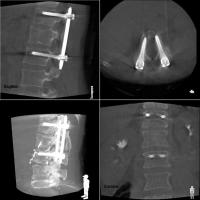

一例として、金属のボルトを骨内に挿入する際に、位置や角度、深さを様々な方向から観察できるほか、装置を回転させて撮影することで、CT画像のような自由な断面像を得ることも可能です。

- 手術手技に必要となる三次元画像情報を、リアルタイムかつ的確に提供します。

高精細なフラットパネルディテクタを搭載しており、従来よりも広い視野でゆがみのない鮮明な画像が得られます。